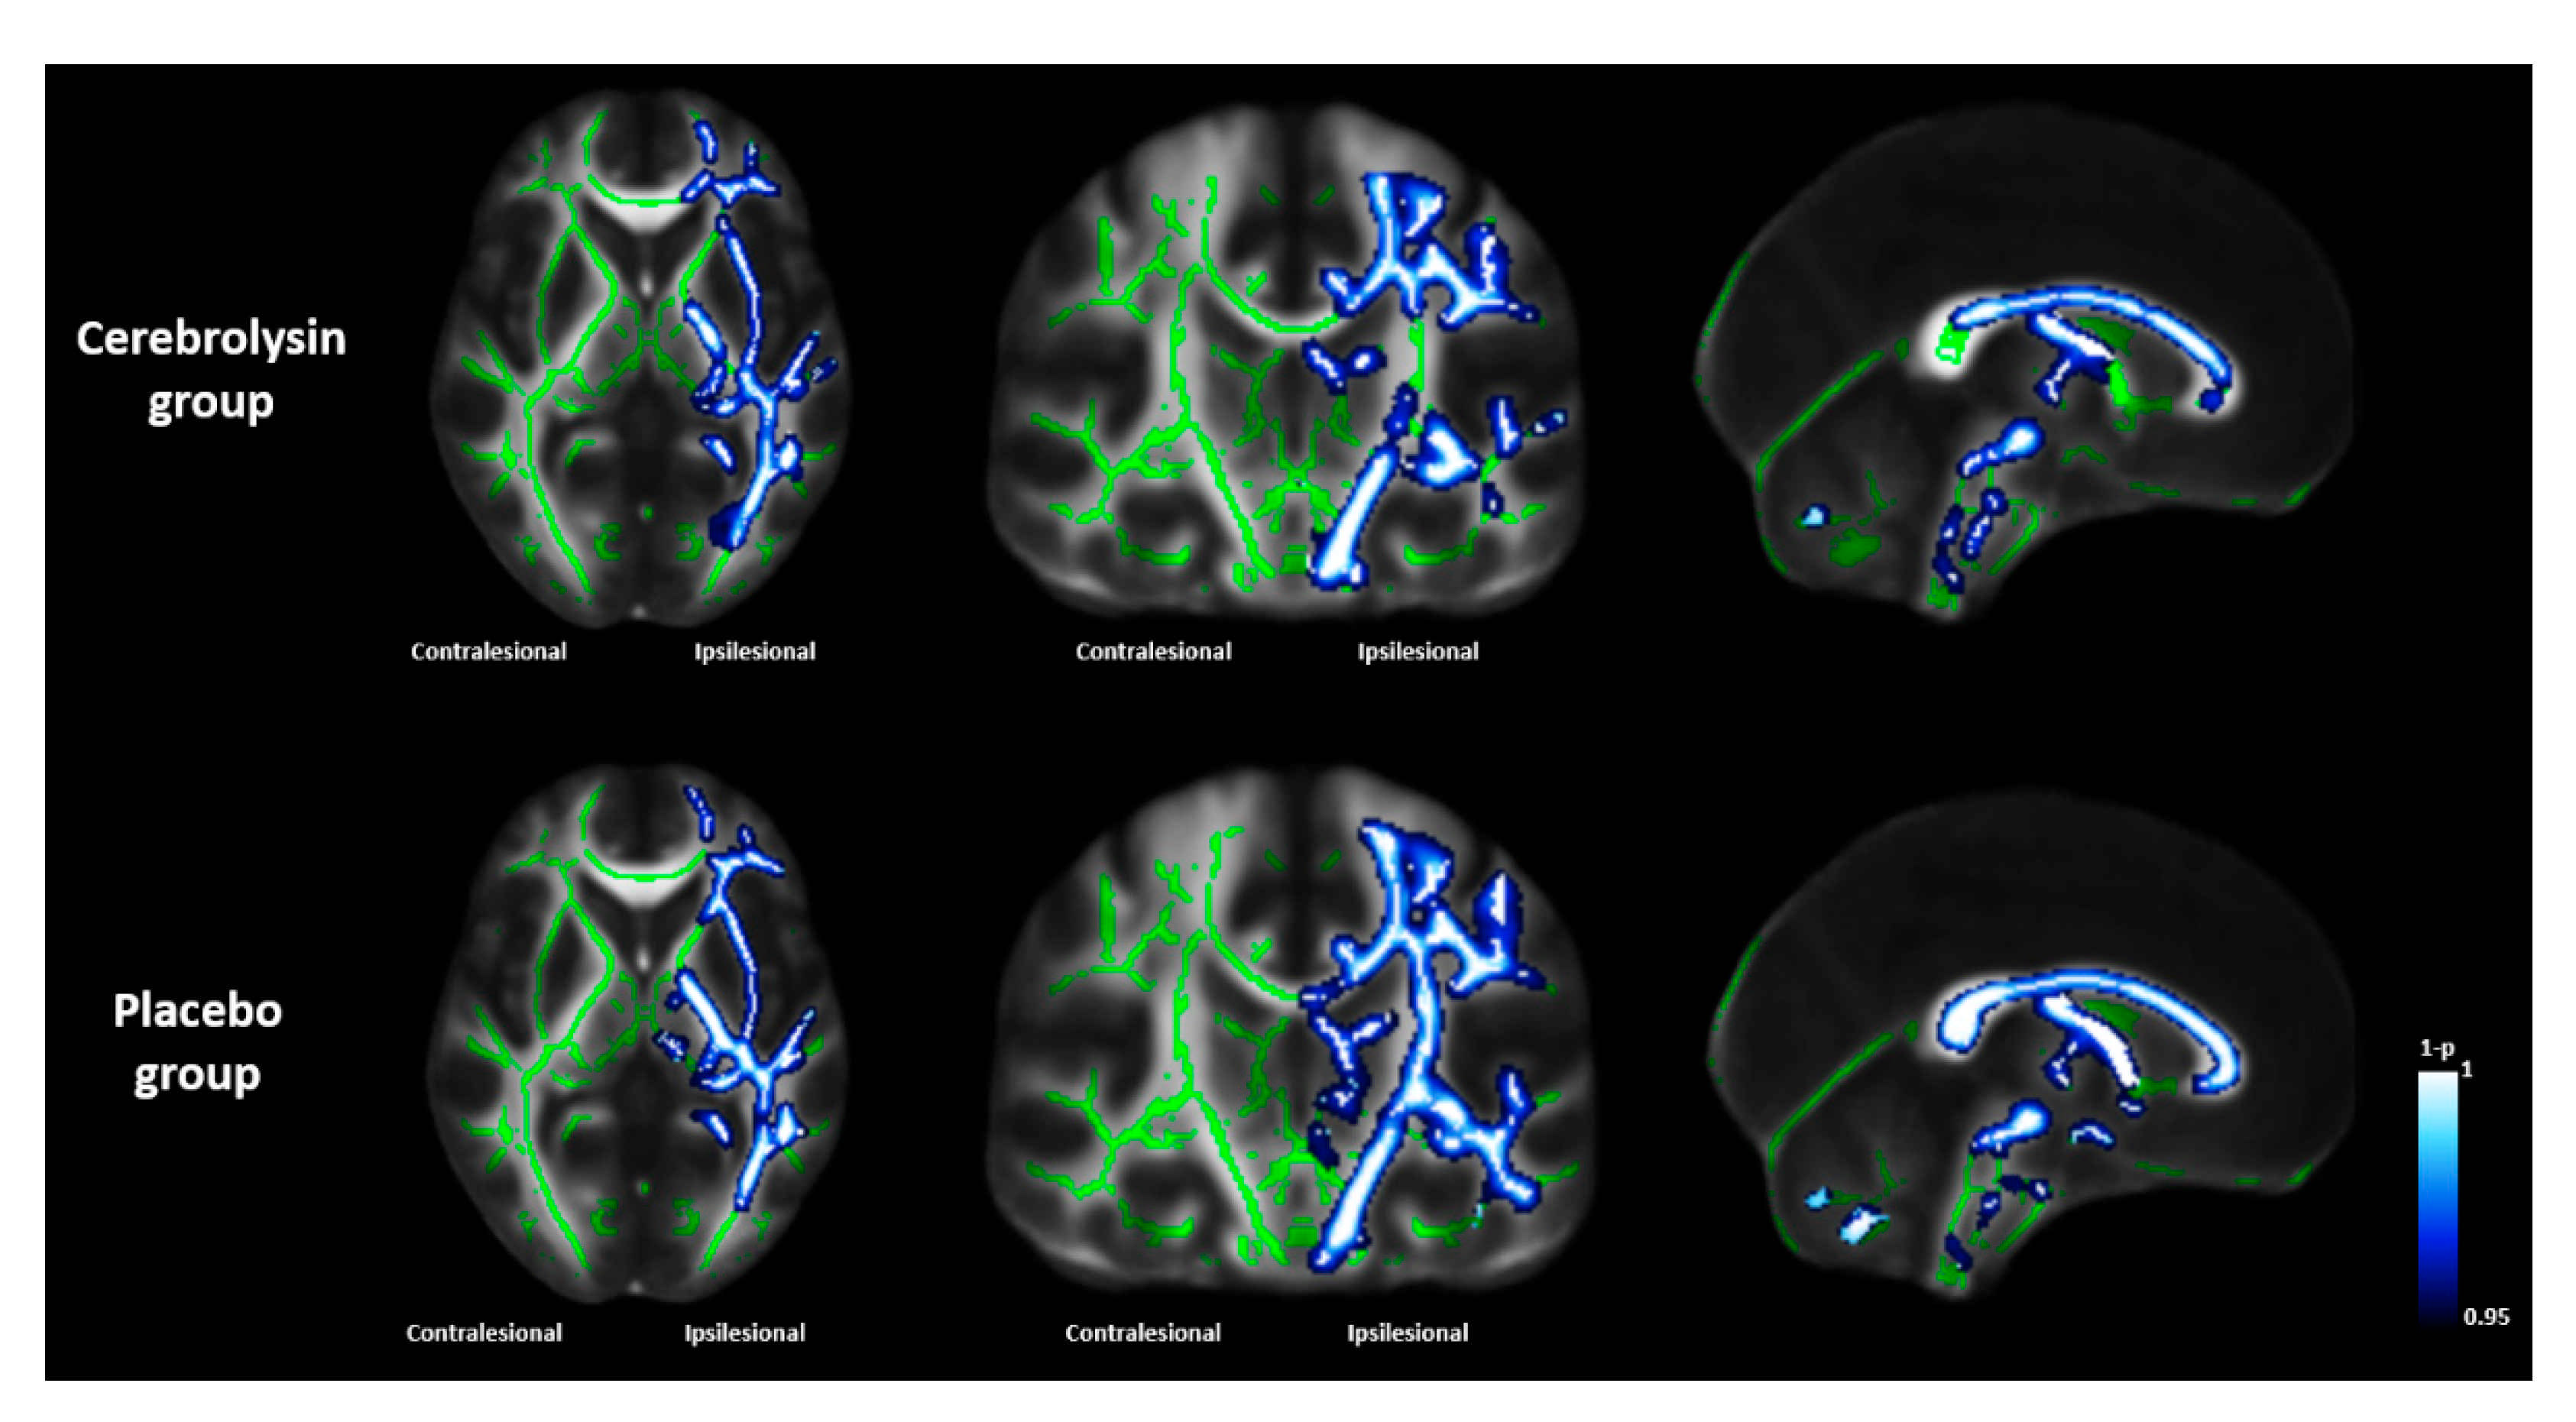

| Corticospinal tract | 0.901 ± 0.070 | 0.816 ± 0.095 | <0.001 * | 0.885 ± 0.084 | 0.757 ± 0.113 | <0.001 * | 0.0167 † |

| Superior corona radiata | 0.887 ± 0.103 | 0.833 ± 0.145 | <0.001 * | 0.859 ± 0.115 | 0.747 ± 0.175 | <0.001 * | 0.0185 † |

| Superior longitudinal fasciculus | 0.917 ± 0.145 | 0.861 ± 0.199 | <0.001 * | 0.908 ± 0.127 | 0.800 ± 0.225 | <0.001 * | 0.0305 † |

| Whole hemispheric tracts | 0.935 ± 0.063 | 0.897 ± 0.082 | <0.001 * | 0.925 ± 0.064 | 0.856 ± 0.110 | <0.001 * | 0.0263 † |

| Genu of corpus callosum | 0.480 ± 0.046 | 0.465 ± 0.050 | <0.001 * | 0.485 ± 0.039 | 0.455 ± 0.056 | <0.001 * | 0.0091 † |

| Body of corpus callosum | 0.516 ± 0.054 | 0.494 ± 0.056 | <0.001 * | 0.523 ± 0.042 | 0.486 ± 0.062 | <0.001 * | 0.0256 † |

| Splenium of corpus callosum | 0.629 ± 0.059 | 0.612 ± 0.061 | <0.001 * | 0.638 ± 0.044 | 0.611 ± 0.058 | <0.001 * | 0.0449 † |